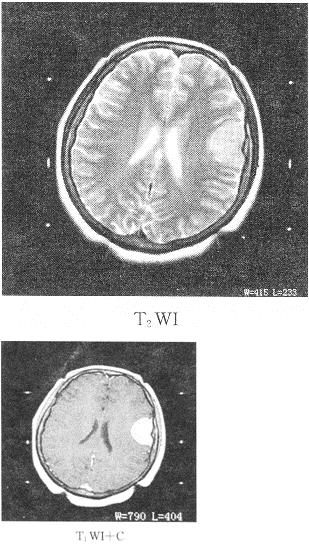

5、 患者女性,34岁,头痛数年,头颅MRI平扫及增强扫描,如图所示最可能的诊断是()。

- A、动脉瘤

- B、脑膜瘤

- C、生殖细胞瘤

- D、星形细胞瘤

- E、三叉神经瘤

【正确答案-参考解析】:参加考试可见 点击进入查看